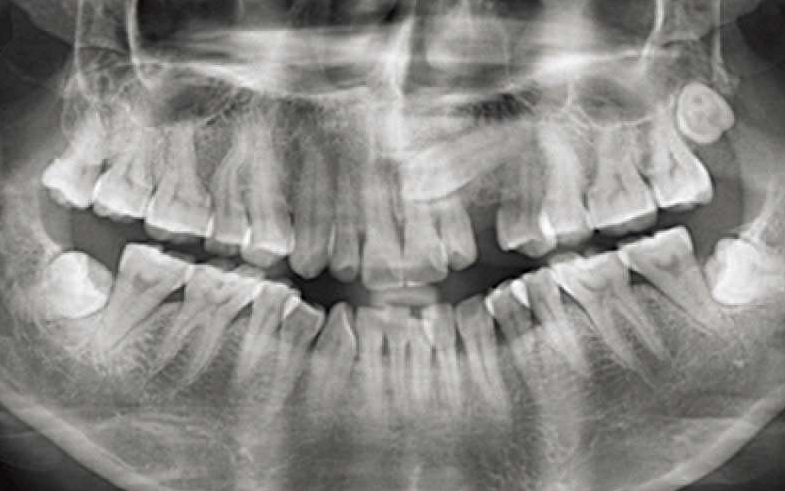

(3)如果患者年龄大于5岁,能够顺利地配合取模型,那我们就要检查:

乳牙Ⅲ、Ⅳ、Ⅴ牙冠的龋坏情况;曲断上看乳牙Ⅲ、Ⅳ、Ⅴ牙根吸收状况,若龋坏不严重可以治愈,或是牙根没有严重地吸收。

解决方案:粘结式RME配合前方牵引。

曲断上检查已经有很明显的乳牙Ⅲ、Ⅳ、Ⅴ牙根吸收,口内检查乳牙Ⅲ、Ⅳ、Ⅴ残冠,或者残根。前牙2-2如果尚未萌出,而且估计一年之内不能完全萌出,此时FRⅢ是最好的解决方案,用FRⅢ等待上前牙2-2萌出。如果反𬌗矫治结束后,前牙2-2还没萌出到正常的咬𬌗状态,这时候的反𬌗矫治效果不稳定,很容易复发。矫治后前牙覆𬌗越深,反𬌗矫治效果越稳定。解决方案:肌功能矫治器FRⅢ(图17)。

年轻恒牙列,如果上4已经完全萌出,适合做上颌RPE配合前方牵引。